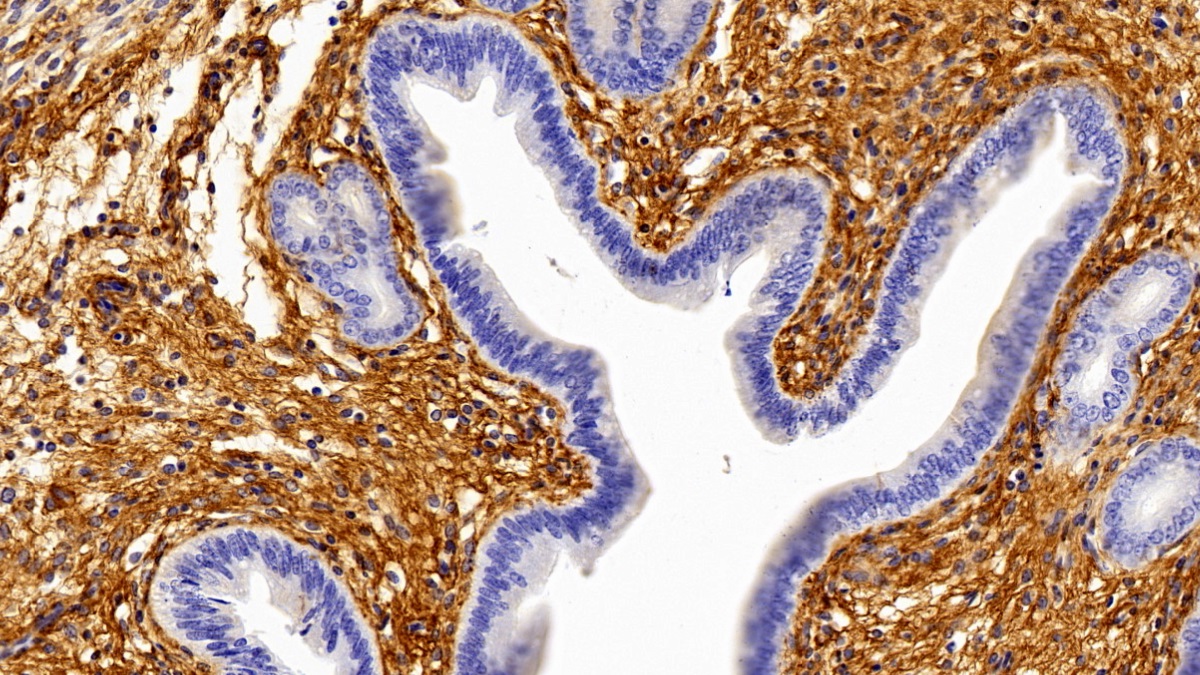

Использование высококачественных первичных антител является неотъемлемым условием получения точных и воспроизводимых результатов в современных научных исследованиях. Например, в рамках онкологического исследования удалось достоверно идентифицировать экспрессию белка PD-L1, что сыграло ключевую роль в оценке потенциальной эффективности иммунотерапии. Применение надежных антител обеспечило стабильность сигнала и высокую специфичность детекции, что позволило получить данные, пригодные для публикации в рецензируемых научных изданиях.